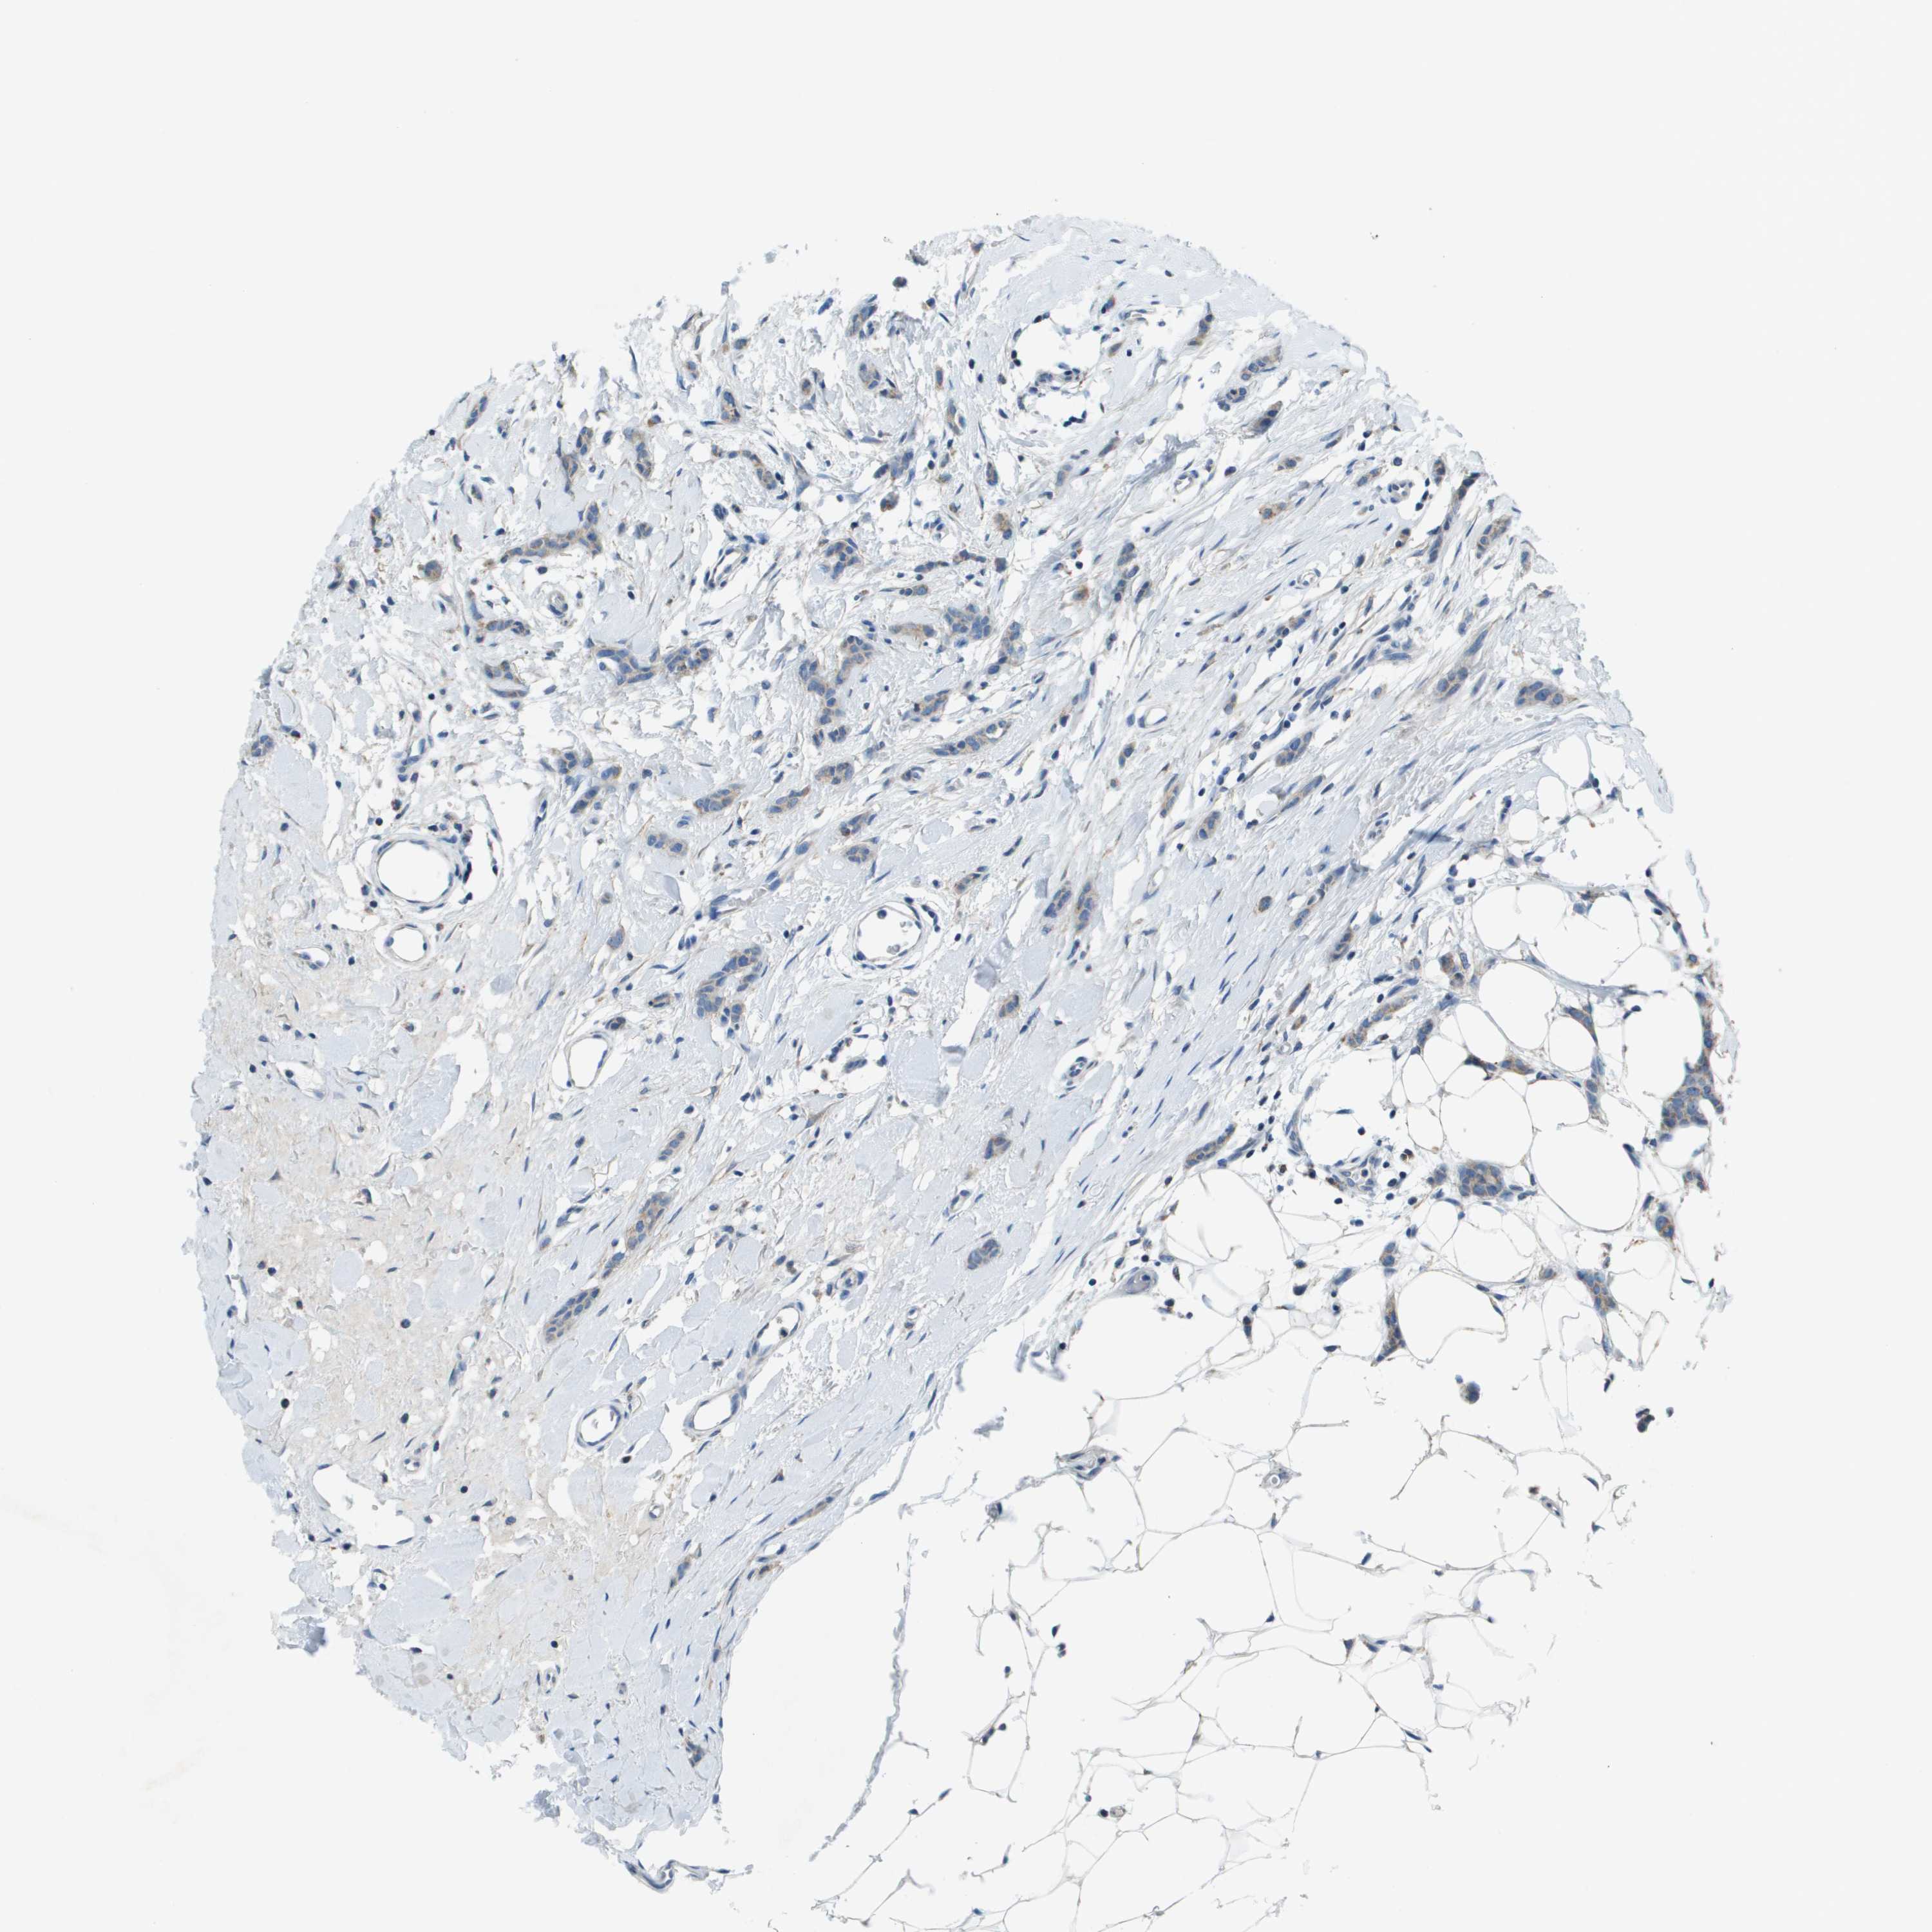

BRCA TCGA BRCA VALIDATION PROTEIN EXPRESSION

Breast cancer

Human cancer